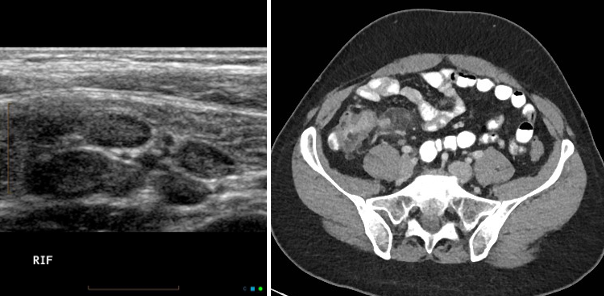

급성 장간막 림프절염 (acute mesenteric lymphadenitis)

정의: 바이러스나 세균감염에 의해 발생하는 장간막 림프절의 염증

증상: RLQ pain, Td, rTd → 임상증상만으로는 충수염과 감별이 어렵고, 동반될 수 있음

진단: 영상 검사상 5mm 이상의 단축 직경을 가진 림프절이 3개 이상 모여있는 경우 진단.

( + normal appendix 확인)